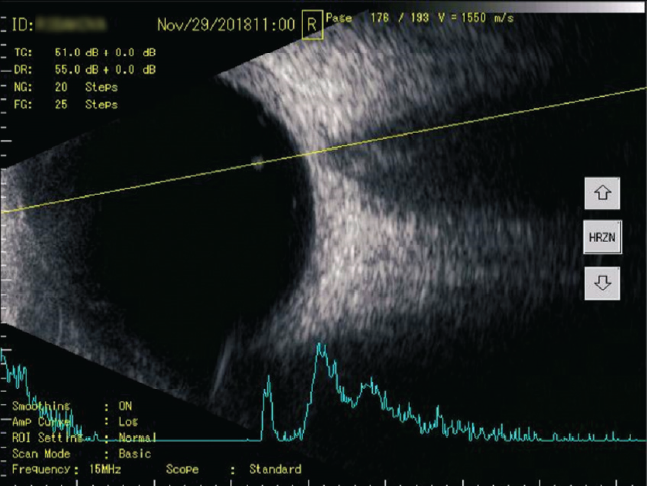

Рис. 3. A- и B-сканирование пациентки П. при первичном обращении. В-скан: в поперечной проекции по меридиану 6 ч — умеренное количество помутнений в стекловидном теле. А-скан: 21 пик низкой эхогенности

Fig. 3. Initial treatment, Patient P.: B-scan: transverse projection along the meridian to 6 hours, moderate amount of “clouding” in the vitreous body. A-scan: 21 peaks of low echogenicity